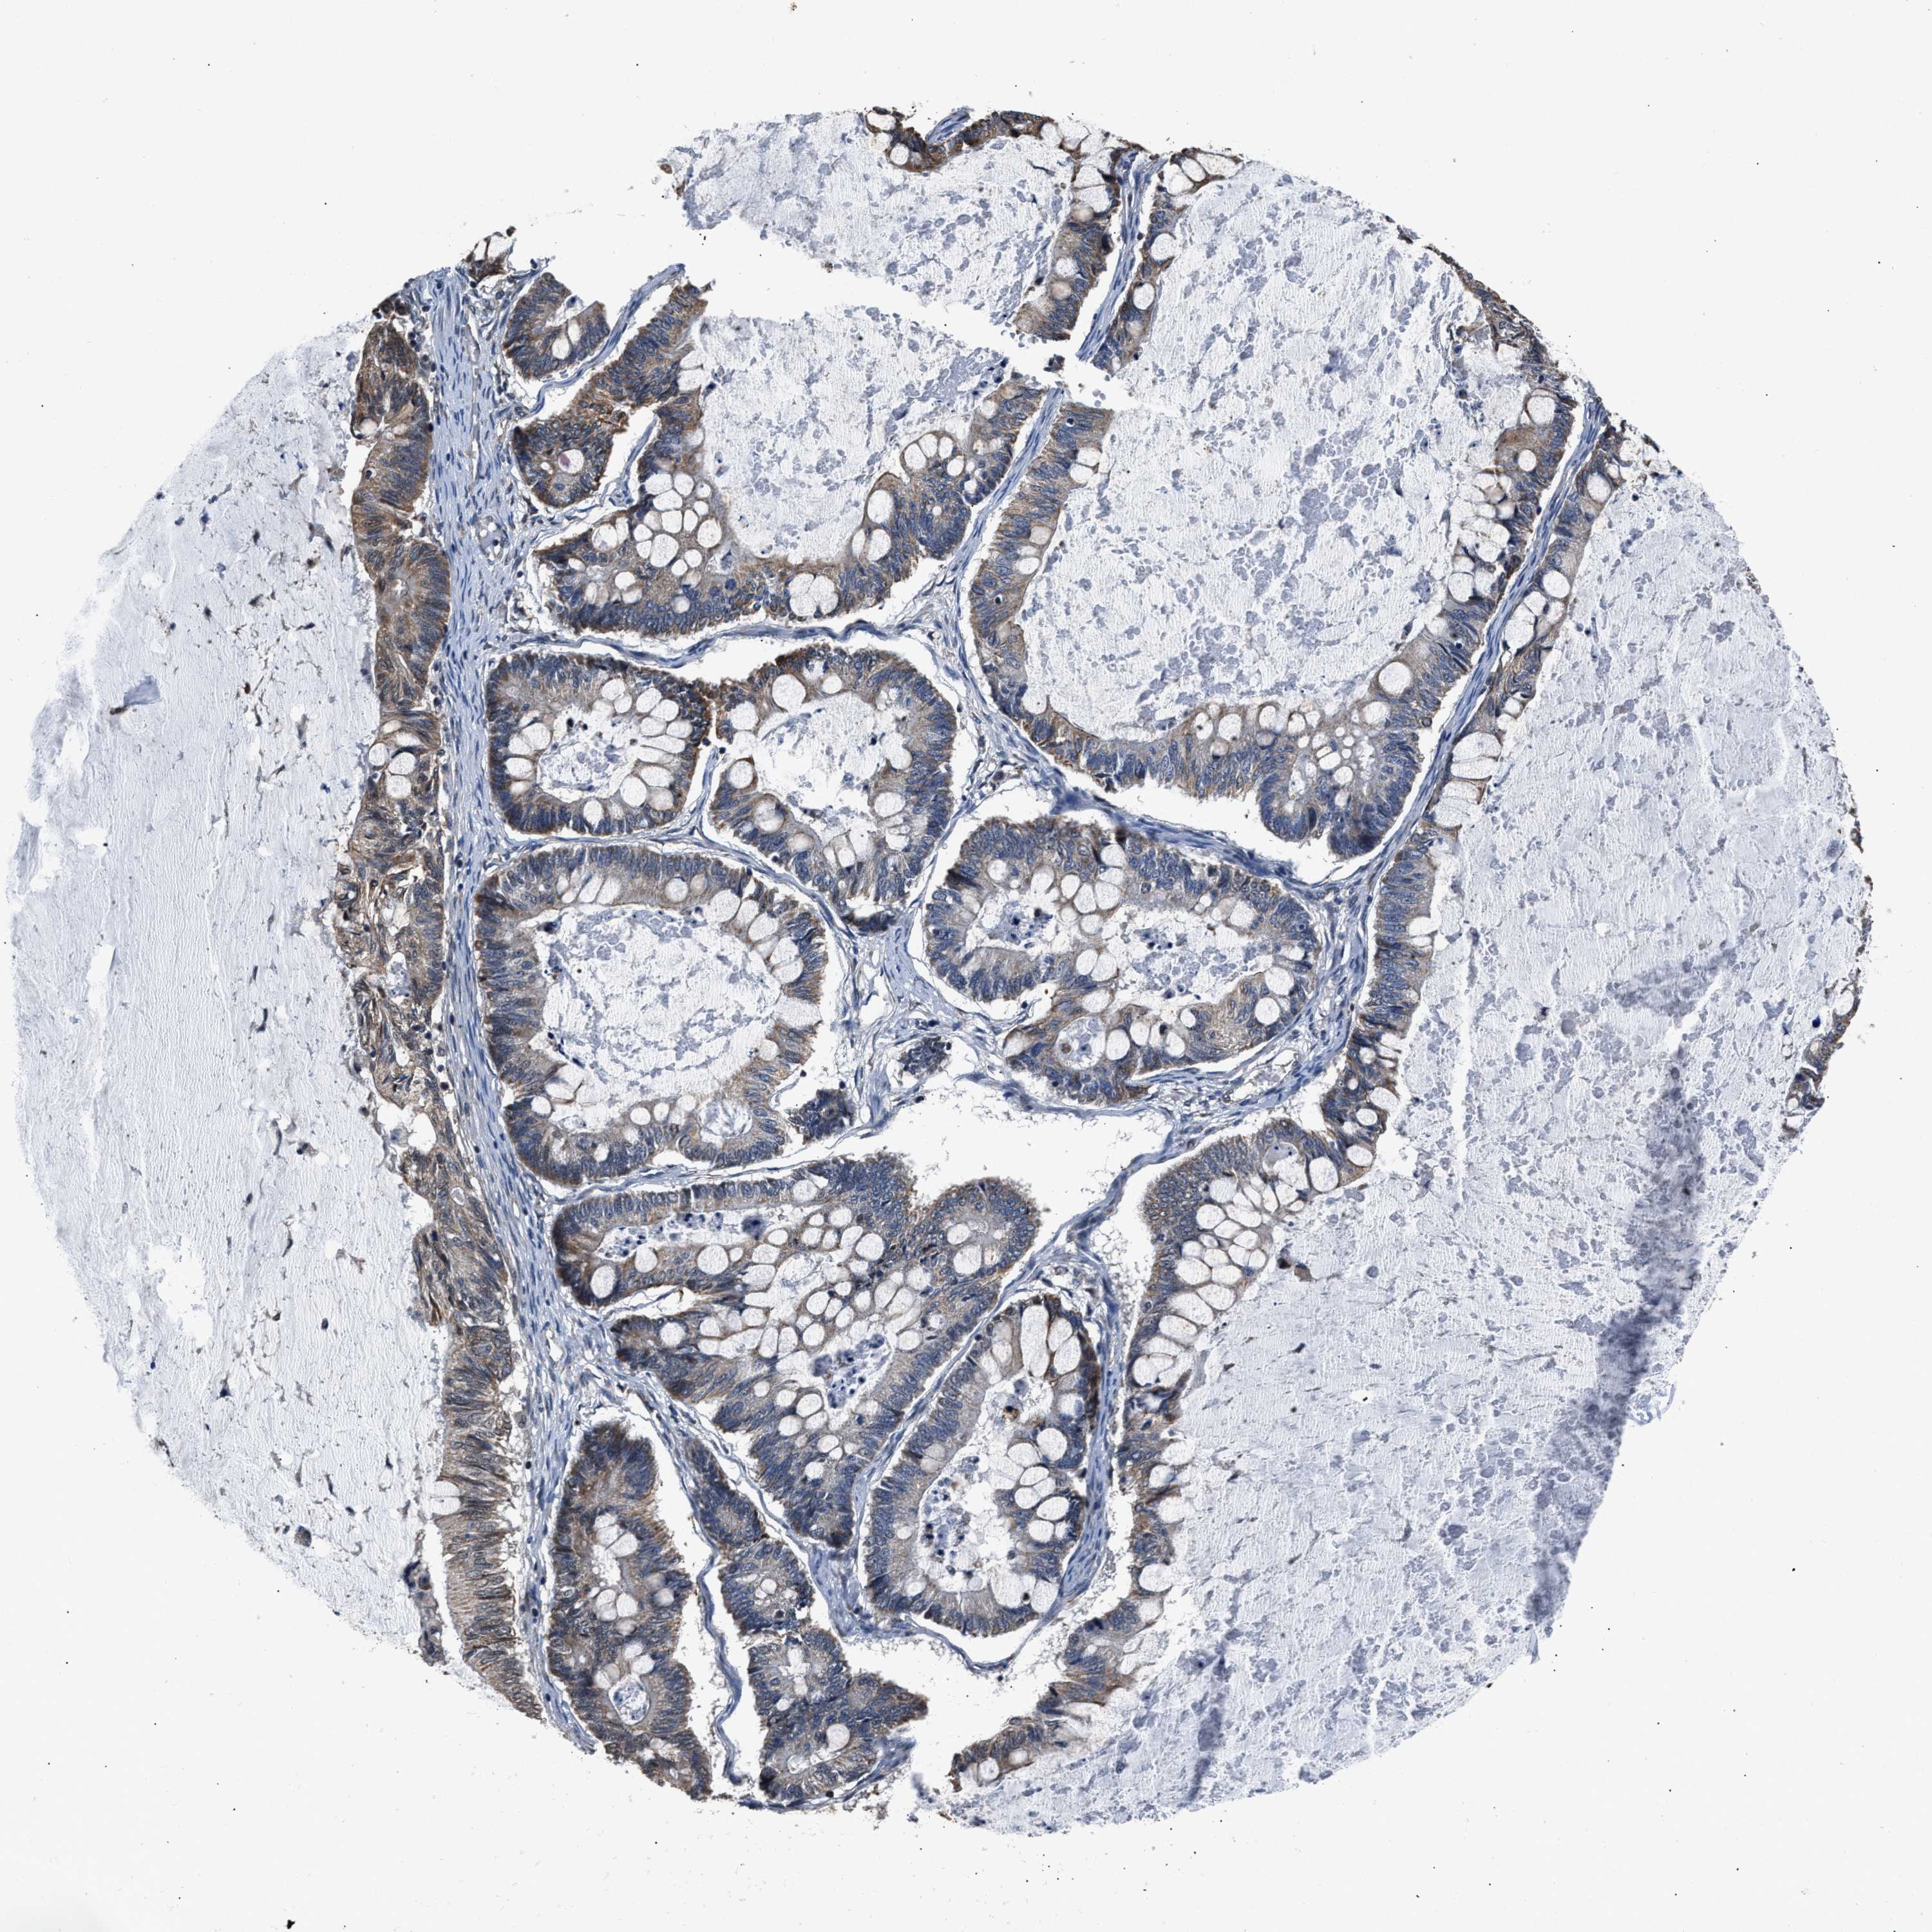

OVARIAN CANCER - Protein expressioni

A mouse-over function shows sample information and annotation data. Click on an image to view it in a full screen mode. Samples can be filtered based on level of antibody staining by selecting one or several of the following categories: high, medium, low and not detected. The assay and annotation is described here.

Note that samples used for immunohistochemistry by the Human Protein Atlas do not correspond to samples in the TCGA dataset.

Antibody stainingi

Antibody staining in the annotated cell types in the current human tissue is reported as not detected, low, medium, or high, based on conventional immunohistochemistry profiling in selected tissues. This score is based on the combination of the staining intensity and fraction of stained cells.

Each image is clickable and will lead to virtual microscopy that enables deeper exploration of all samples and also displays staining intensity scores, fraction scores and subcellular localization as well as patient and tissue information for each sample.

Antibody HPA020536

Staining

High

Medium

Low

Not detected

Intensity

Strong

Moderate

Weak

Negative

Quantity

>75%

75%-25%

<25%

None

Location

Nuclear

Cytoplasmic/membranous

Cytoplasmic/membranous,nuclear

Cystadenocarcinoma, serous, NOS

Carcinoma, endometroid

Cystadenocarcinoma, mucinous, NOS

Carcinoma, NOS